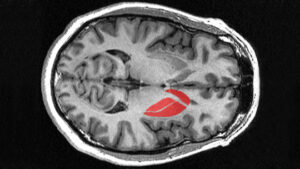

In biology, the term “ganglion” is used to designate the masses of tissue that form in cellular systems. Specifically in neurology, this term usually refers to a mass or group of nerve cell bodies present in most living organisms. Its main function is to carry nerve impulses from the periphery to the center, or vice versa.

In this sense, a “nervous ganglion” is the agglomeration of somas or neuronal bodies that are located in the autonomic nervous system It is mainly responsible for connecting the peripheral nervous system with the central nervous system, both in an efferent sense (from the central nervous system to the sensory organs) and afferent sense (from the sensory organs to the central nervous system).

Therefore, a nervous ganglion is broadly composed of cell bodies of afferent nerves, cell bodies of efferent nerves, and neuronal axons Likewise, it can be divided into two large subtypes according to the specific function they perform within the peripheral nervous system.